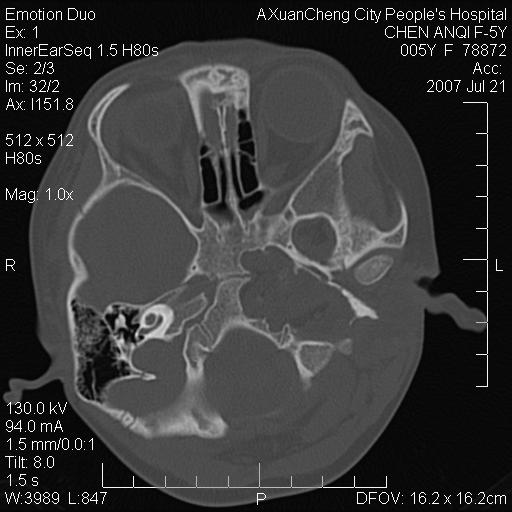

标题: PED0273:5岁,左耳流脓痛疼一周,颅底骨质破坏 [打印本页]

标题: PED0273:5岁,左耳流脓痛疼一周,颅底骨质破坏

患儿5岁,左耳流脓痛疼一周,左外耳道肉芽组织填塞 软组织窗显示病灶内结节状低密度影为气体密度

左侧中耳炎并胆脂瘤,左颞骨岩部骨质破坏并颅内感染积气。

考虑化脓性中耳乳突炎伴胆脂肪瘤形成并左颞叶感染,不除外合并嗜酸性肉芽肿.